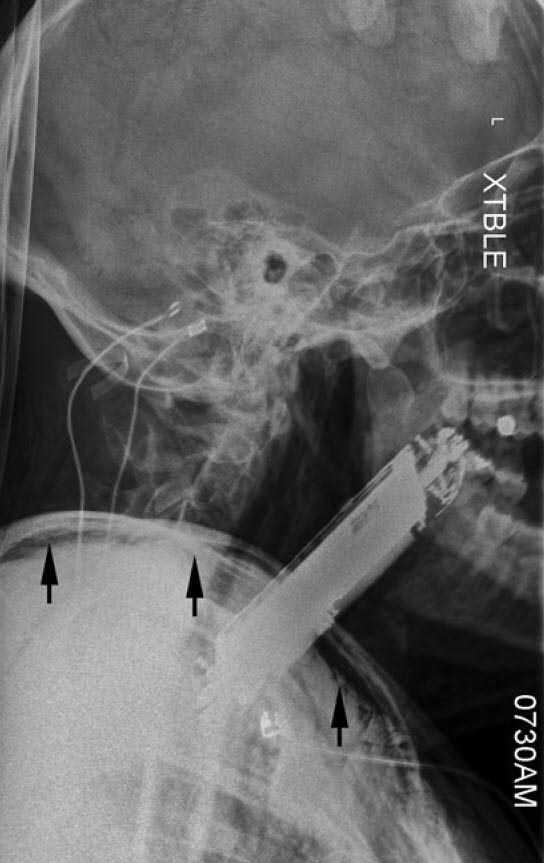

یک پزشک - مرد ۳۵ ساله‌ای بدون مشکل قبلی پزشکی، به اورژانس آمد، او بعد از مصرف ماده روانگردان فن‌سیکلیدین یا PCP دچار توهمات شنوایی دستوری شده بود.

تحت تأثیر این توهم‌ها، او گوشی هوشمند خود را که ابعادش ۴ در ۸ سانتیمتر بود، بلعیده بود!

در بدو ورود او آشفته، اما هوشیار بود، بزاقش جاری بود و تنگی نفس (دیسترس) در حد متوسط داشت.

گوشی موبایل به وضوح وارد حلق (اوروفارنکس) او شده بود و این قسمت را به جلو منحرف کرده بود. سرعت تنفس او بالا رفته بود و در هر دقیقه به ۲۴ تنفس رسیده بود. میزان اشباع اکسیژن او ۹۲ درصد بود و سرعت ضربان قلب‌اش ۱۳۱ ضربه در دقیقه بود، فشار خونش هم ۱۳۷ روی ۶۴ میلیمتر جیوه بود.

بعد از همه اینها پزشکان متوجه شدند که نوموتوراکس دوطرفه و آمفیزم زیر پوستی در گردن و اندام فوقانی دارد.

یعنی هوا وارد حفره جنب او شده بود، در این شرایط هوایی که به صورت غیرطبیعی در حفره جنب جمع می‌شود به ریه‌ها فشار می‌آورد و باعث می‌شود ریه‌های نتوانند به صورت طبیعی از هوا پر شوند، حتی امکان دارد، این فشار باعث اختلال در ورود و خروج خون به قلب شود که بسیار خطرناک است.

سی تی اسکن درخواست شد و تشخیص را تأیید کرد، همچینن سی تی نشان داد که هوا در قسمت میانی قفسه سینه (مدیاستن) جمع شده است.